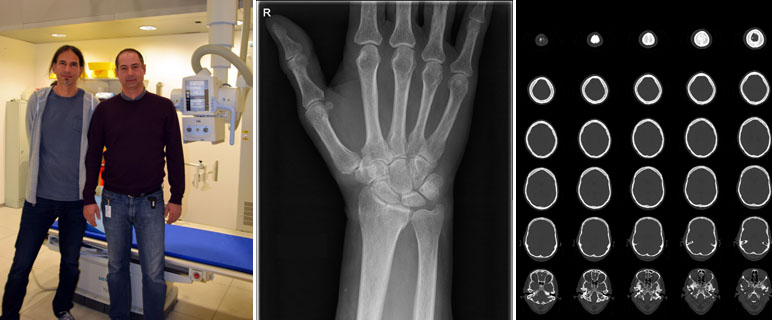

Das Department Radiologie wurde für die hohen Qualitätsstandards insbesondere im Strahlenschutz ausgezeichnet: Derzeit sind die Innsbrucker Univ.-Kliniken für Radiologie und Neuroradiologie die beiden einzigen in Österreich, die von der Europäischen Gesellschaft für Radiologie im Rahmen der“ EuroSafe Imaging Stars“-Kampagne mit fünf Sternen ausgezeichnet wurde. Das Department Radiologie nimmt damit eine Vorbildfunktion ein. Weitere Einrichtungen werden dem Beispiel Innsbruck folgen.

Die hervorragende Bewertung ist eine Auszeichnung für die seit Jahren gesetzten Maßnahmen zur Qualitätssicherung und -kontrolle. Ein wichtiges Ziel ist der sichere Umgang mit der verwendeten Strahlung und nach Möglichkeit eine Weiterentwicklung der verwendeten Technik zur Reduzierung der verwendeten Dosis. Patient:innen erhalten die höchstmögliche Sicherheit. „Der erste Schritt zur Dosisreduzierung ist die genaue Dokumentation der verwendeten Strahlenintensität. Nur wenn wir die Dosis genau kennen, können wir auch Maßnahmen zur Optimierung setzen“, erklären Dr. Michael Verius und Mag. Pavle Torbica. Die beiden Medizinphysiker sind die Strahlenschutzbeauftragten am Department Radiologie. Gemeinsam mit ihrem Kollegen Mag. Robert Eder haben sie eine Software entwickelt, die bereits seit Mitte 2012 angewendet und laufend verbessert wird. „Damit können wir für jede Patientin und jeden Patienten die verwendete Strahlendosis erfassen, speichern und analysieren“, erklärt Michael Verius. Damit nimmt das Department Radiologie eine Vorreiterrolle in Bezug auf das Dosis-Management in Österreich ein. „Für die behandelnden Ärzt:innen ermöglicht die Datenerfassung es frühzeitig zu erkennen, wenn vorgeschriebene Belastungshöchstgrenzen überschritten werden“, sagt Pavle Torbica. Die erfassten Daten sind auch relevant für die Weiterentwicklung auf dem Gebiet der Radiologie. Im Rahmen von Forschungsprojekten werden die Werte analysiert. Die Erkenntnisse sollen dabei helfen, die Strahlendosis bei einer Untersuchung oder Behandlung weiter zu optimieren, ohne die Bildqualität zu verschlechtern. Insbesondere im Bereich der Computertomographie (CT) sind hier noch weitere Verbesserungen möglich. „CT-Untersuchungen machen zwar nur 9 bis 10 Prozent aller Untersuchungen aus. Ihr Anteil an der Kollektivdosis beträgt aber trotzdem 65 bis 70 Prozent“, weiß Michael Verius. Ähnliches gilt für durchleuchtungsgesteuerte therapeutische Eingriffe wie z. B. die katheterbasierte Behandlung von Gefäßerkrankungen.